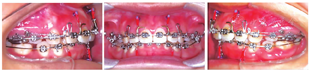

矫治结束时患者Ⅱ类面型得到很好的掩饰,面部肌肉自然放松,侧貌协调,鼻唇颏关系协调。上下牙列排列整齐无拥挤无散在间隙,前牙覆

、覆盖正常,磨牙、尖牙达到中性关系,中线齐,咬合关系正常。颞下颌关节检查张口度、张口型正常,双侧关节无弹响、疼痛等不适。矫治后曲面断层片(图3D):显示全口牙根无明显异常,牙槽骨无明显吸收。头颅侧位X线片(图3C)矫治结束后CBCT(图3J~M)示:双侧关节与治疗前未见明显差异,上下前牙牙根皆位于牙槽骨内。矫治前后头影测量重叠图及测量值见(图4、表1)。